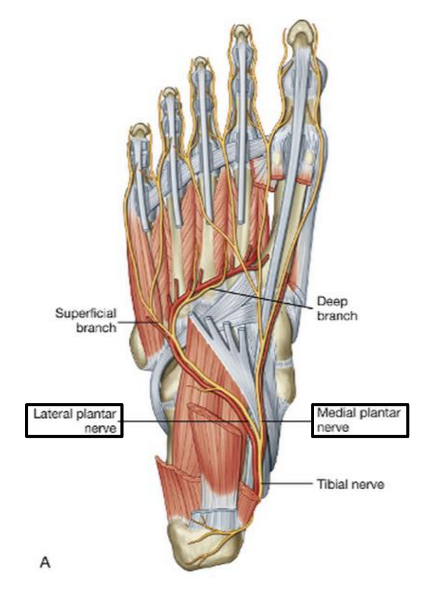

Into which nerves does tibial nerve bifurcate?

medial and lateral plantar nerve

Which muscles are innervated by the medial plantar nerve?

abductor hallucis and flexor digitorum brevis

1 medial lumbrical

flexor hallucis brevis

Which muscles are innervated by lateral plantar nerve in the first layer of dorsal surface?

abductor digiti minimi

origin and distribution of tibial nerve

O sciatic nerve

C forms as sciatic nerve bifurcates at apex of popliteal fossa; descends through popliteal fossa; runs inferior to tibialis posterior with posterior tibial vessels; terminates beneath flexor retinaculum by dividing into medial and lateral plantar nerves

D supplies plantar flexor muscles of the posterior compartment of the leg and knee joint

origin and distribution of lateral plantar nerve

O tibial nerve beneath flexor retinaculum

D abductor digiti minimi muscle (foot), flexor digiti minimi brevis muscle (foot), quadratus plantae, 3 lateral lumbricals of the foot, adductor hallucis muscle, plantar interossei muscles, dorsal interossei muscles

origin and distribution of medial plantar nerve

O tibial nerve beneath flexor retinaculum

D abductor hallucis, the flexor digitorum brevis, the flexor hallucis brevis, and the first lumbrical

branches of lateral plantar nerve

deep branch

superficial branch

branches of medial plantar n

common plantar digital nerves --> proper plantar digital nerves